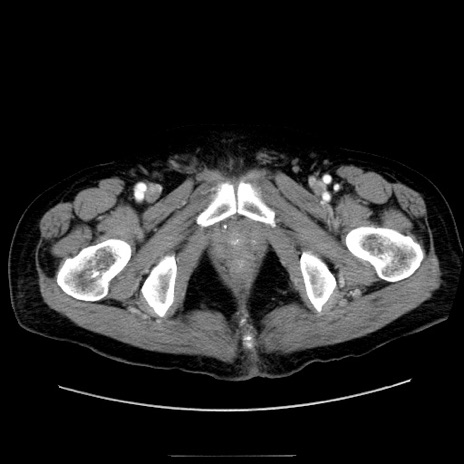

症例30(横断像)

【症例】80歳代男性

【主訴】臍周囲痛

【現病歴】約6時間前から臍下部痛が出現。次第に腹部膨隆・背部痛も生じてきたため来院。背部痛の場所は変化しない。

【既往歴】腎盂腎炎

【身体所見】意識清明、BT 36.3℃、BP  131/87mmHg、P 87bpm、SpO2 100%(RA)、臍周囲自発痛・圧痛あり、反跳痛なし、自発痛部位に一致して板状硬あり、腹部膨隆、腸雑音減弱、CVA tenderness両側陰性。

【データ】WBC 19600、CRP 0.33